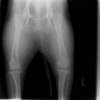

術前正面像

術後左後肢正面像

術前のTPAは左後肢33.1°右後肢26.8°でしたがTPLO実施により左後肢5.5°右後肢12°に矯正されました。